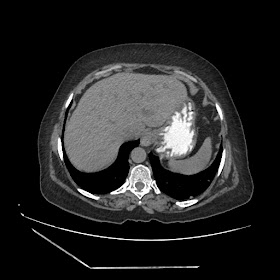

A 70 years old woman with Obstractive jaundice & palpable GB

Latest Radiological images: